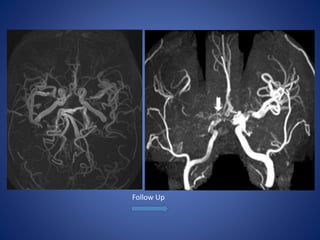

14 yr male child, K/C/O sickle cell anemia, Transcranial doppler revealed Rt. MCA

narrowing.

Courtesy : Dr M. M Shroff. Hospital for Sick Children Toronto

Follow Up

14 yr malechild, K/C/O sickle cell anemia, Transcranial doppler revealed Rt. MCA narrowing. Courtesy : Dr M. M Shroff. Hospital for Sick Children Toronto